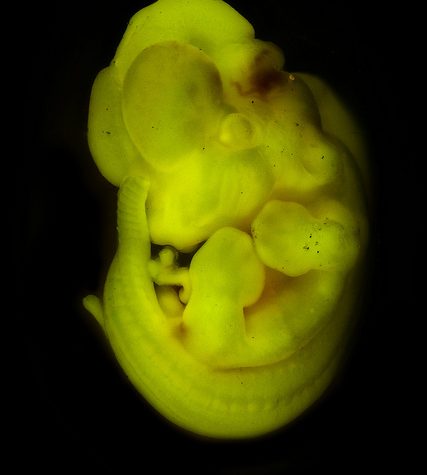

The laboratory mouse is a small mammal of the order Rodentia which is bred and used for scientific research. Laboratory mice are usually of the species Mus musculus. They are the most commonly used mammalian research model and are used for research in genetics, psychology, medicine and other scientific disciplines. Mice belong to the Euarchontoglires clade, which includes humans. This close relationship, the associated high homology with humans, their ease of maintenance and handling, and their high reproduction rate, make mice particularly suitable models for human-oriented research. The laboratory mouse genome has been sequenced and many mouse genes have human homologues.[1]

The laboratory mouse is a small mammal of the order Rodentia which is bred and used for scientific research. Laboratory mice are usually of the species Mus musculus. They are the most commonly used mammalian research model and are used for research in genetics, psychology, medicine and other scientific disciplines. Mice belong to the Euarchontoglires clade, which includes humans. This close relationship, the associated high homology with humans, their ease of maintenance and handling, and their high reproduction rate, make mice particularly suitable models for human-oriented research. The laboratory mouse genome has been sequenced and many mouse genes have human homologues.[1]

The laboratory mouse is a small mammal of the order Rodentia which is bred and used for scientific research. Laboratory mice are usually of the species Mus musculus. They are the most commonly used mammalian research model and are used for research in genetics, psychology, medicine and other scientific disciplines. Mice belong to the Euarchontoglires clade, which includes humans. This close relationship, the associated high homology with humans, their ease of maintenance and handling, and their high reproduction rate, make mice particularly suitable models for human-oriented research. The laboratory mouse genome has been sequenced and many mouse genes have human homologues.[1]

The laboratory mouse is a small mammal of the order Rodentia which is bred and used for scientific research. Laboratory mice are usually of the species Mus musculus. They are the most commonly used mammalian research model and are used for research in genetics, psychology, medicine and other scientific disciplines. Mice belong to the Euarchontoglires clade, which includes humans. This close relationship, the associated high homology with humans, their ease of maintenance and handling, and their high reproduction rate, make mice particularly suitable models for human-oriented research. The laboratory mouse genome has been sequenced and many mouse genes have human homologues.[1]

The laboratory mouse is a small mammal of the order Rodentia which is bred and used for scientific research. Laboratory mice are usually of the species Mus musculus. They are the most commonly used mammalian research model and are used for research in genetics, psychology, medicine and other scientific disciplines. Mice belong to the Euarchontoglires clade, which includes humans. This close relationship, the associated high homology with humans, their ease of maintenance and handling, and their high reproduction rate, make mice particularly suitable models for human-oriented research. The laboratory mouse genome has been sequenced and many mouse genes have human homologues.[1]

The laboratory mouse is a small mammal of the order Rodentia which is bred and used for scientific research. Laboratory mice are usually of the species Mus musculus. They are the most commonly used mammalian research model and are used for research in genetics, psychology, medicine and other scientific disciplines. Mice belong to the Euarchontoglires clade, which includes humans. This close relationship, the associated high homology with humans, their ease of maintenance and handling, and their high reproduction rate, make mice particularly suitable models for human-oriented research. The laboratory mouse genome has been sequenced and many mouse genes have human homologues.[1]

The laboratory mouse is a small mammal of the order Rodentia which is bred and used for scientific research. Laboratory mice are usually of the species Mus musculus. They are the most commonly used mammalian research model and are used for research in genetics, psychology, medicine and other scientific disciplines. Mice belong to the Euarchontoglires clade, which includes humans. This close relationship, the associated high homology with humans, their ease of maintenance and handling, and their high reproduction rate, make mice particularly suitable models for human-oriented research. The laboratory mouse genome has been sequenced and many mouse genes have human homologues.[1]

The laboratory mouse is a small mammal of the order Rodentia which is bred and used for scientific research. Laboratory mice are usually of the species Mus musculus. They are the most commonly used mammalian research model and are used for research in genetics, psychology, medicine and other scientific disciplines. Mice belong to the Euarchontoglires clade, which includes humans. This close relationship, the associated high homology with humans, their ease of maintenance and handling, and their high reproduction rate, make mice particularly suitable models for human-oriented research. The laboratory mouse genome has been sequenced and many mouse genes have human homologues.[1]

The laboratory mouse is a small mammal of the order Rodentia which is bred and used for scientific research. Laboratory mice are usually of the species Mus musculus. They are the most commonly used mammalian research model and are used for research in genetics, psychology, medicine and other scientific disciplines. Mice belong to the Euarchontoglires clade, which includes humans. This close relationship, the associated high homology with humans, their ease of maintenance and handling, and their high reproduction rate, make mice particularly suitable models for human-oriented research. The laboratory mouse genome has been sequenced and many mouse genes have human homologues.[1]

The laboratory mouse is a small mammal of the order Rodentia which is bred and used for scientific research. Laboratory mice are usually of the species Mus musculus. They are the most commonly used mammalian research model and are used for research in genetics, psychology, medicine and other scientific disciplines. Mice belong to the Euarchontoglires clade, which includes humans. This close relationship, the associated high homology with humans, their ease of maintenance and handling, and their high reproduction rate, make mice particularly suitable models for human-oriented research. The laboratory mouse genome has been sequenced and many mouse genes have human homologues.[1]

The laboratory mouse is a small mammal of the order Rodentia which is bred and used for scientific research. Laboratory mice are usually of the species Mus musculus. They are the most commonly used mammalian research model and are used for research in genetics, psychology, medicine and other scientific disciplines. Mice belong to the Euarchontoglires clade, which includes humans. This close relationship, the associated high homology with humans, their ease of maintenance and handling, and their high reproduction rate, make mice particularly suitable models for human-oriented research. The laboratory mouse genome has been sequenced and many mouse genes have human homologues.[1]